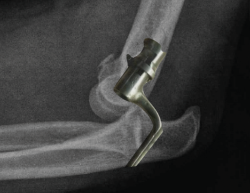

Figura 6. Radiografía lateral de codo tras una maniobra de reducción de una luxación donde puede verse cómo el eje longitudinal del radio se encuentra alineado con la bisectriz del capitellum. Además, puede observarse un drop sign positivo (flecha negra). Este signo corresponde a un aumento de la distancia ulnohumeral de > 3 mm.

Tras la reducción de un codo luxado, en la evaluación radiográfica, el eje longitudinal del radio debe pasar por la bisectriz del capitellum (Figura 6). En ocasiones, puede apreciarse también un drop sign positivo(17)(Figura 6), que corresponde a un aumento de la distancia ulnohumeral de > 3 mm. Son signos de inestabilidad persistente de codo una mal alineación radiocapitelar tras la reducción y un drop sign persistente en las radiografías de control sucesivas.